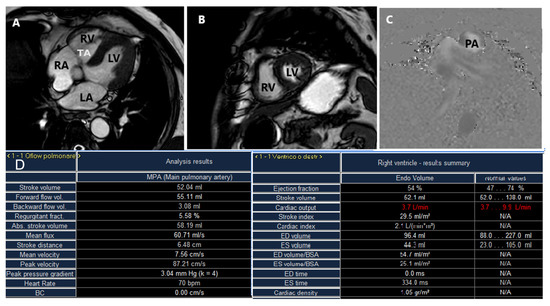

2.3. Cardiac Magnetic Resonance

4.2. Cardiac Computed Tomography and Cardiac Magnetic Resonance